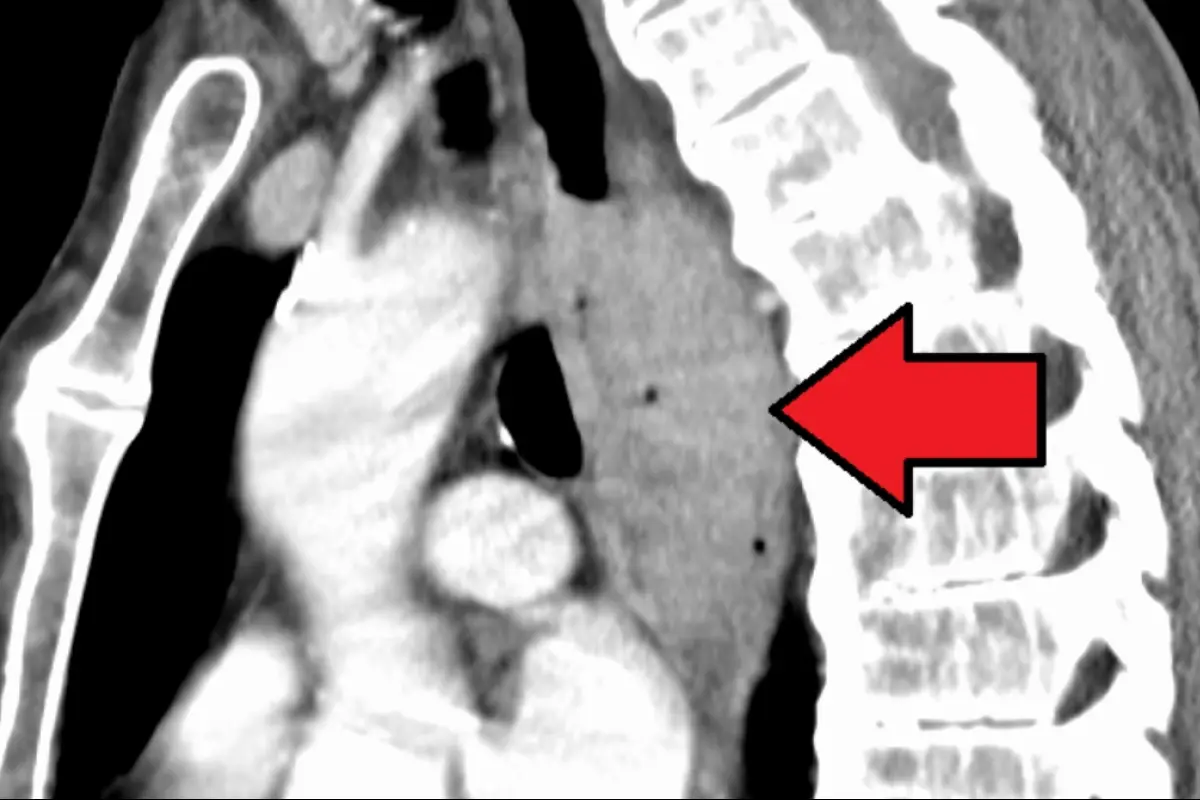

La detección temprana del cáncer de esófago es fundamental para obtener resultados positivos en la supervivencia. La Dra. Blackmon enfatiza que los tratamientos de invasión mínima son posibles cuando se detecta el cáncer en etapas iniciales. Esto permite preservar el esófago y realizar cirugías como la esofagectomía, en la que se extirpa una parte pequeña o el esófago en su totalidad, dependiendo de la etapa y el grado del tumor. La forma en que se extirpa y reconstruye el esófago varía según cada caso.

En comparación con la esofagectomía abierta, la esofagectomía de invasión mínima ofrece varias ventajas para el paciente. Tras este procedimiento, el paciente experimenta una recuperación más rápida y siente menos dolor. Además, se realiza una reconstrucción del esófago adaptada a cada situación particular, lo que favorece el proceso de rehabilitación y mejora la calidad de vida del paciente.